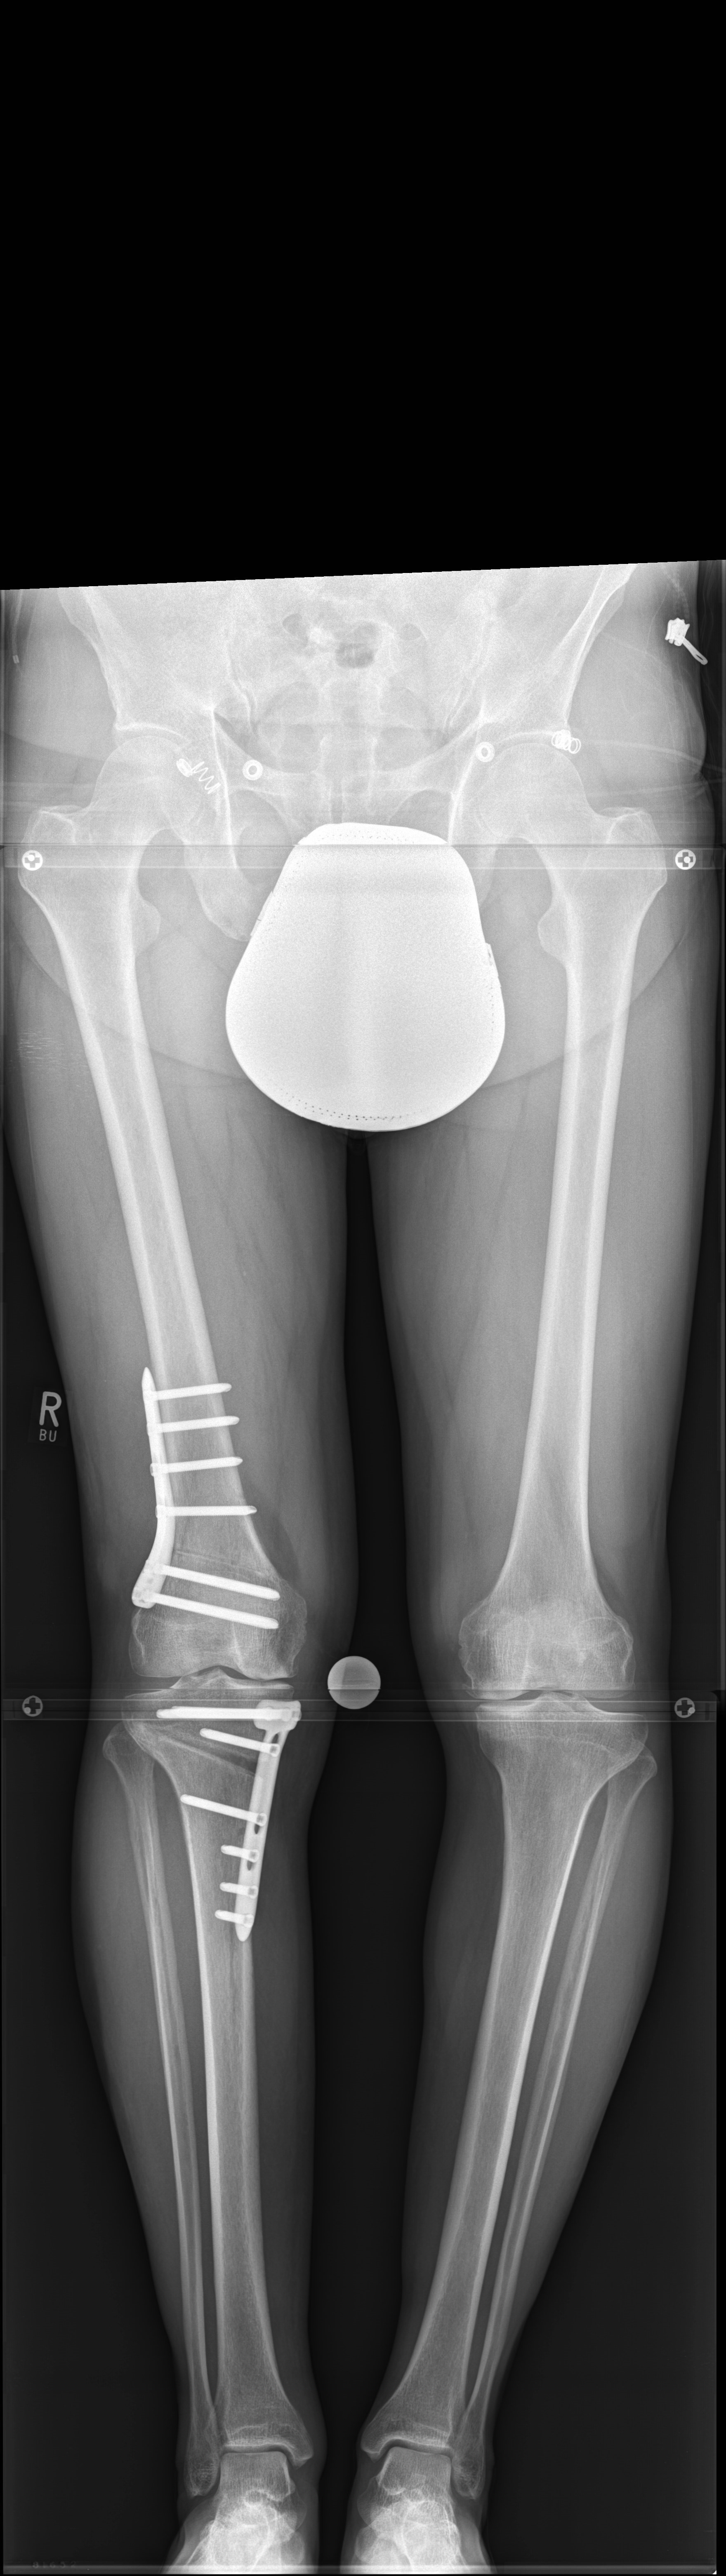

Case 2

(Case provided by Steffen Schröter)

A 52-year-old man with a posttraumatic deformity 2 years after tibial plateau fracture AO/OTA 41C3.3e, PL, PM complained of pain after a normal working day. The patient was a heavy smoker. Activities like sports or hiking were discontinued. Surprisingly ligaments in the coronal and sagittal planes were stable. There was no effusion. Pain was localized in the medial compartment. The range of motion was limited to 0/0/130°. The deformity was corrected with a high tibial osteotomy.